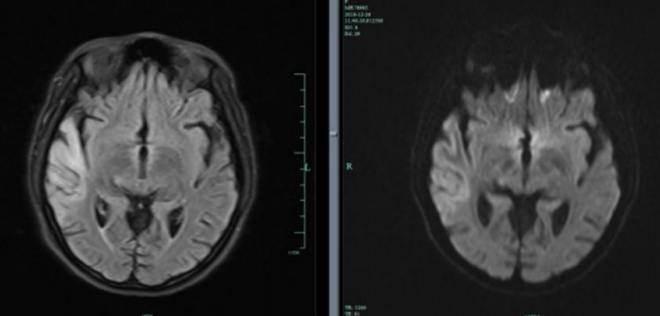

患者女性,26岁,“反复四肢抽搐 11年,言语不利、反应迟钝4天”入院。患者15岁时首次出现癫痫样发作,表现为口吐白沫,头向右侧歪斜,四肢抽搐,伴有意识丧失,持续数秒钟后自行缓解,间隔一段时候后再发,每次发作前多有发热,头痛诱因,诊断为“癫痫”,予德巴金治疗,自行服用半年后停用。患者分别在19岁,21岁,25岁以及今年11月份出现上述癫痫样发作,患者家属诉患者每次癫 痫发作时持续时间均不足1分钟,发作频繁,间歇期逐渐缩短。患者4天前出现言语不利、反应迟钝。

2018.11.3核磁如下:

2018.12.27核磁如下:

2019.1.19核磁如下:

答案:MELAS。其影像典型表现:CT:部分见基底节钙化。MRI:T2WI,FLAIR,DWI序列上相应的高信号;ADC可为高信号,低信号或混杂信号,提示细胞毒性水肿和血管源 性水肿同时存在;磁共振波谱(MRS)提示脑部乳酸的存在。病灶多分布在皮层和皮层下白质,深部皮层不受累;急性到亚急性时期病灶变化可有明显波动,迁移至完全消失;反复发作后脑萎缩。